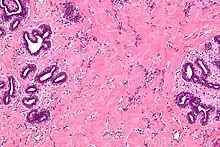

High magnification micrograph of pseudoangiomatous stromal hyperplasia showing the characteristic small, anastomosing blood vessel-like channels. H&E stain. | |

Pseudoangiomatous stromal hyperplasia (PASH) is an overgrowth of myofibroblastic cells in the breast. It has an appearance similar to fibroadenomatoid changes.[1]

The important differential diagnosis is angiosarcoma, from which it was first differentiated in 1986.[2]